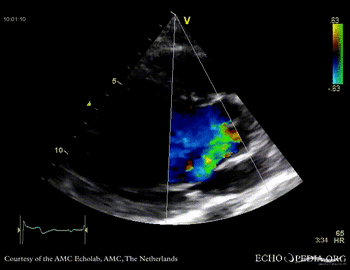

Case 10